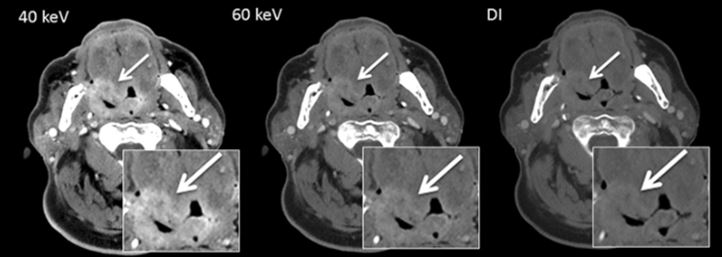

Is Dual-Energy CT beneficial for head and neck imaging?

Article: Comparison of dual- and single-source dual-energy CT in head and neck imaging